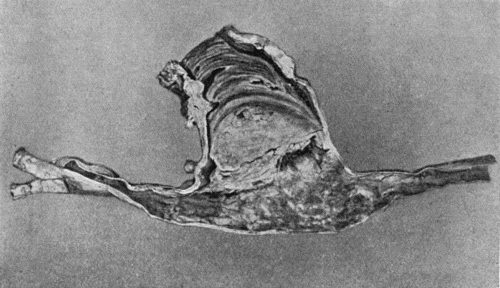

Another modification is to raise the flap but leave it connected at both ends like the piers of a bridge; this method is well suited to defects of skin on the dorsum of the fingers, hand and forearm, the bridge of skin is raised from the abdominal wall and the hand is passed beneath it and securely fixed in position; after an interval of 14 to 21 days, when the flap is assured of its blood supply, the piers of the bridge are divided (Fig. 1). With undermining it is usually easy to bring the edges of the gap in the abdominal wall together, even in children; the skin flap on the dorsum of the hand appears rather thick and prominent—almost like the pad of a boxing-glove—for some time, but the restoration of function in the capacity to flex the fingers is gratifying in the extreme.

Fig. 1.—Ulcer of back of Hand covered by flap of skin raised from anterior abdominal wall. The lateral edges of the flap are divided after the graft has adhered.